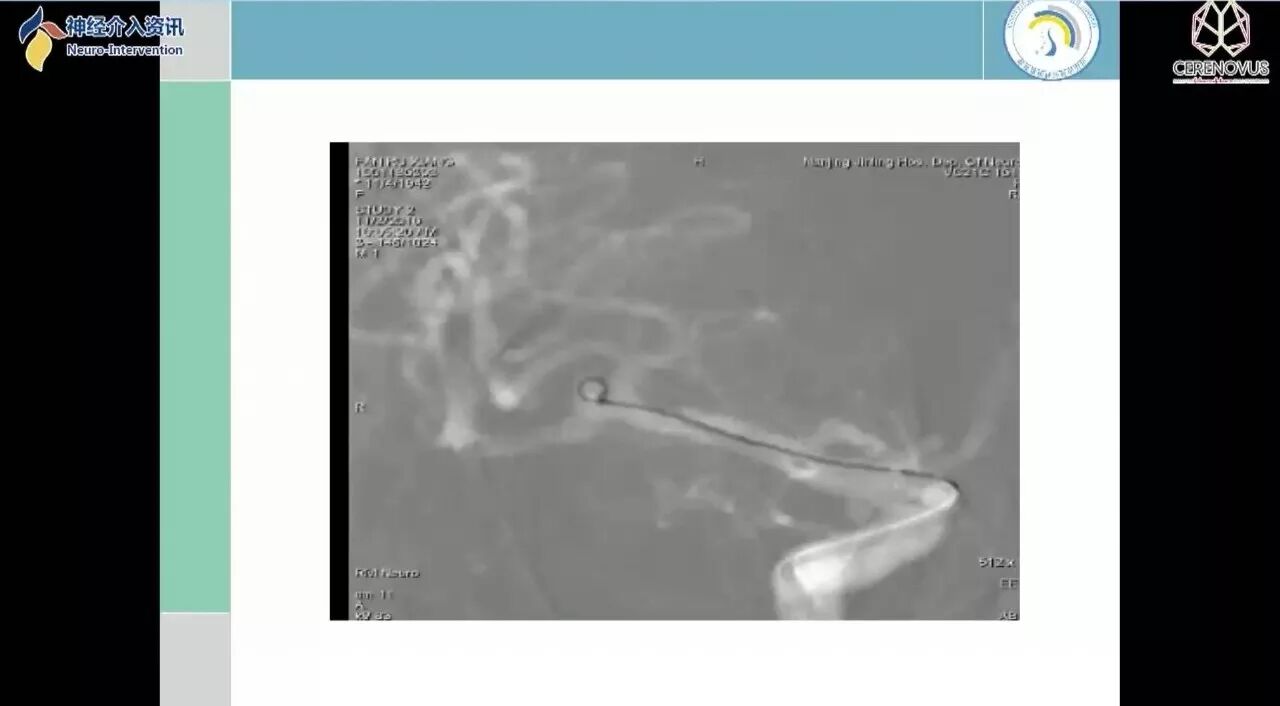

Galaxy弹簧圈在小动脉瘤栓塞术中的应用